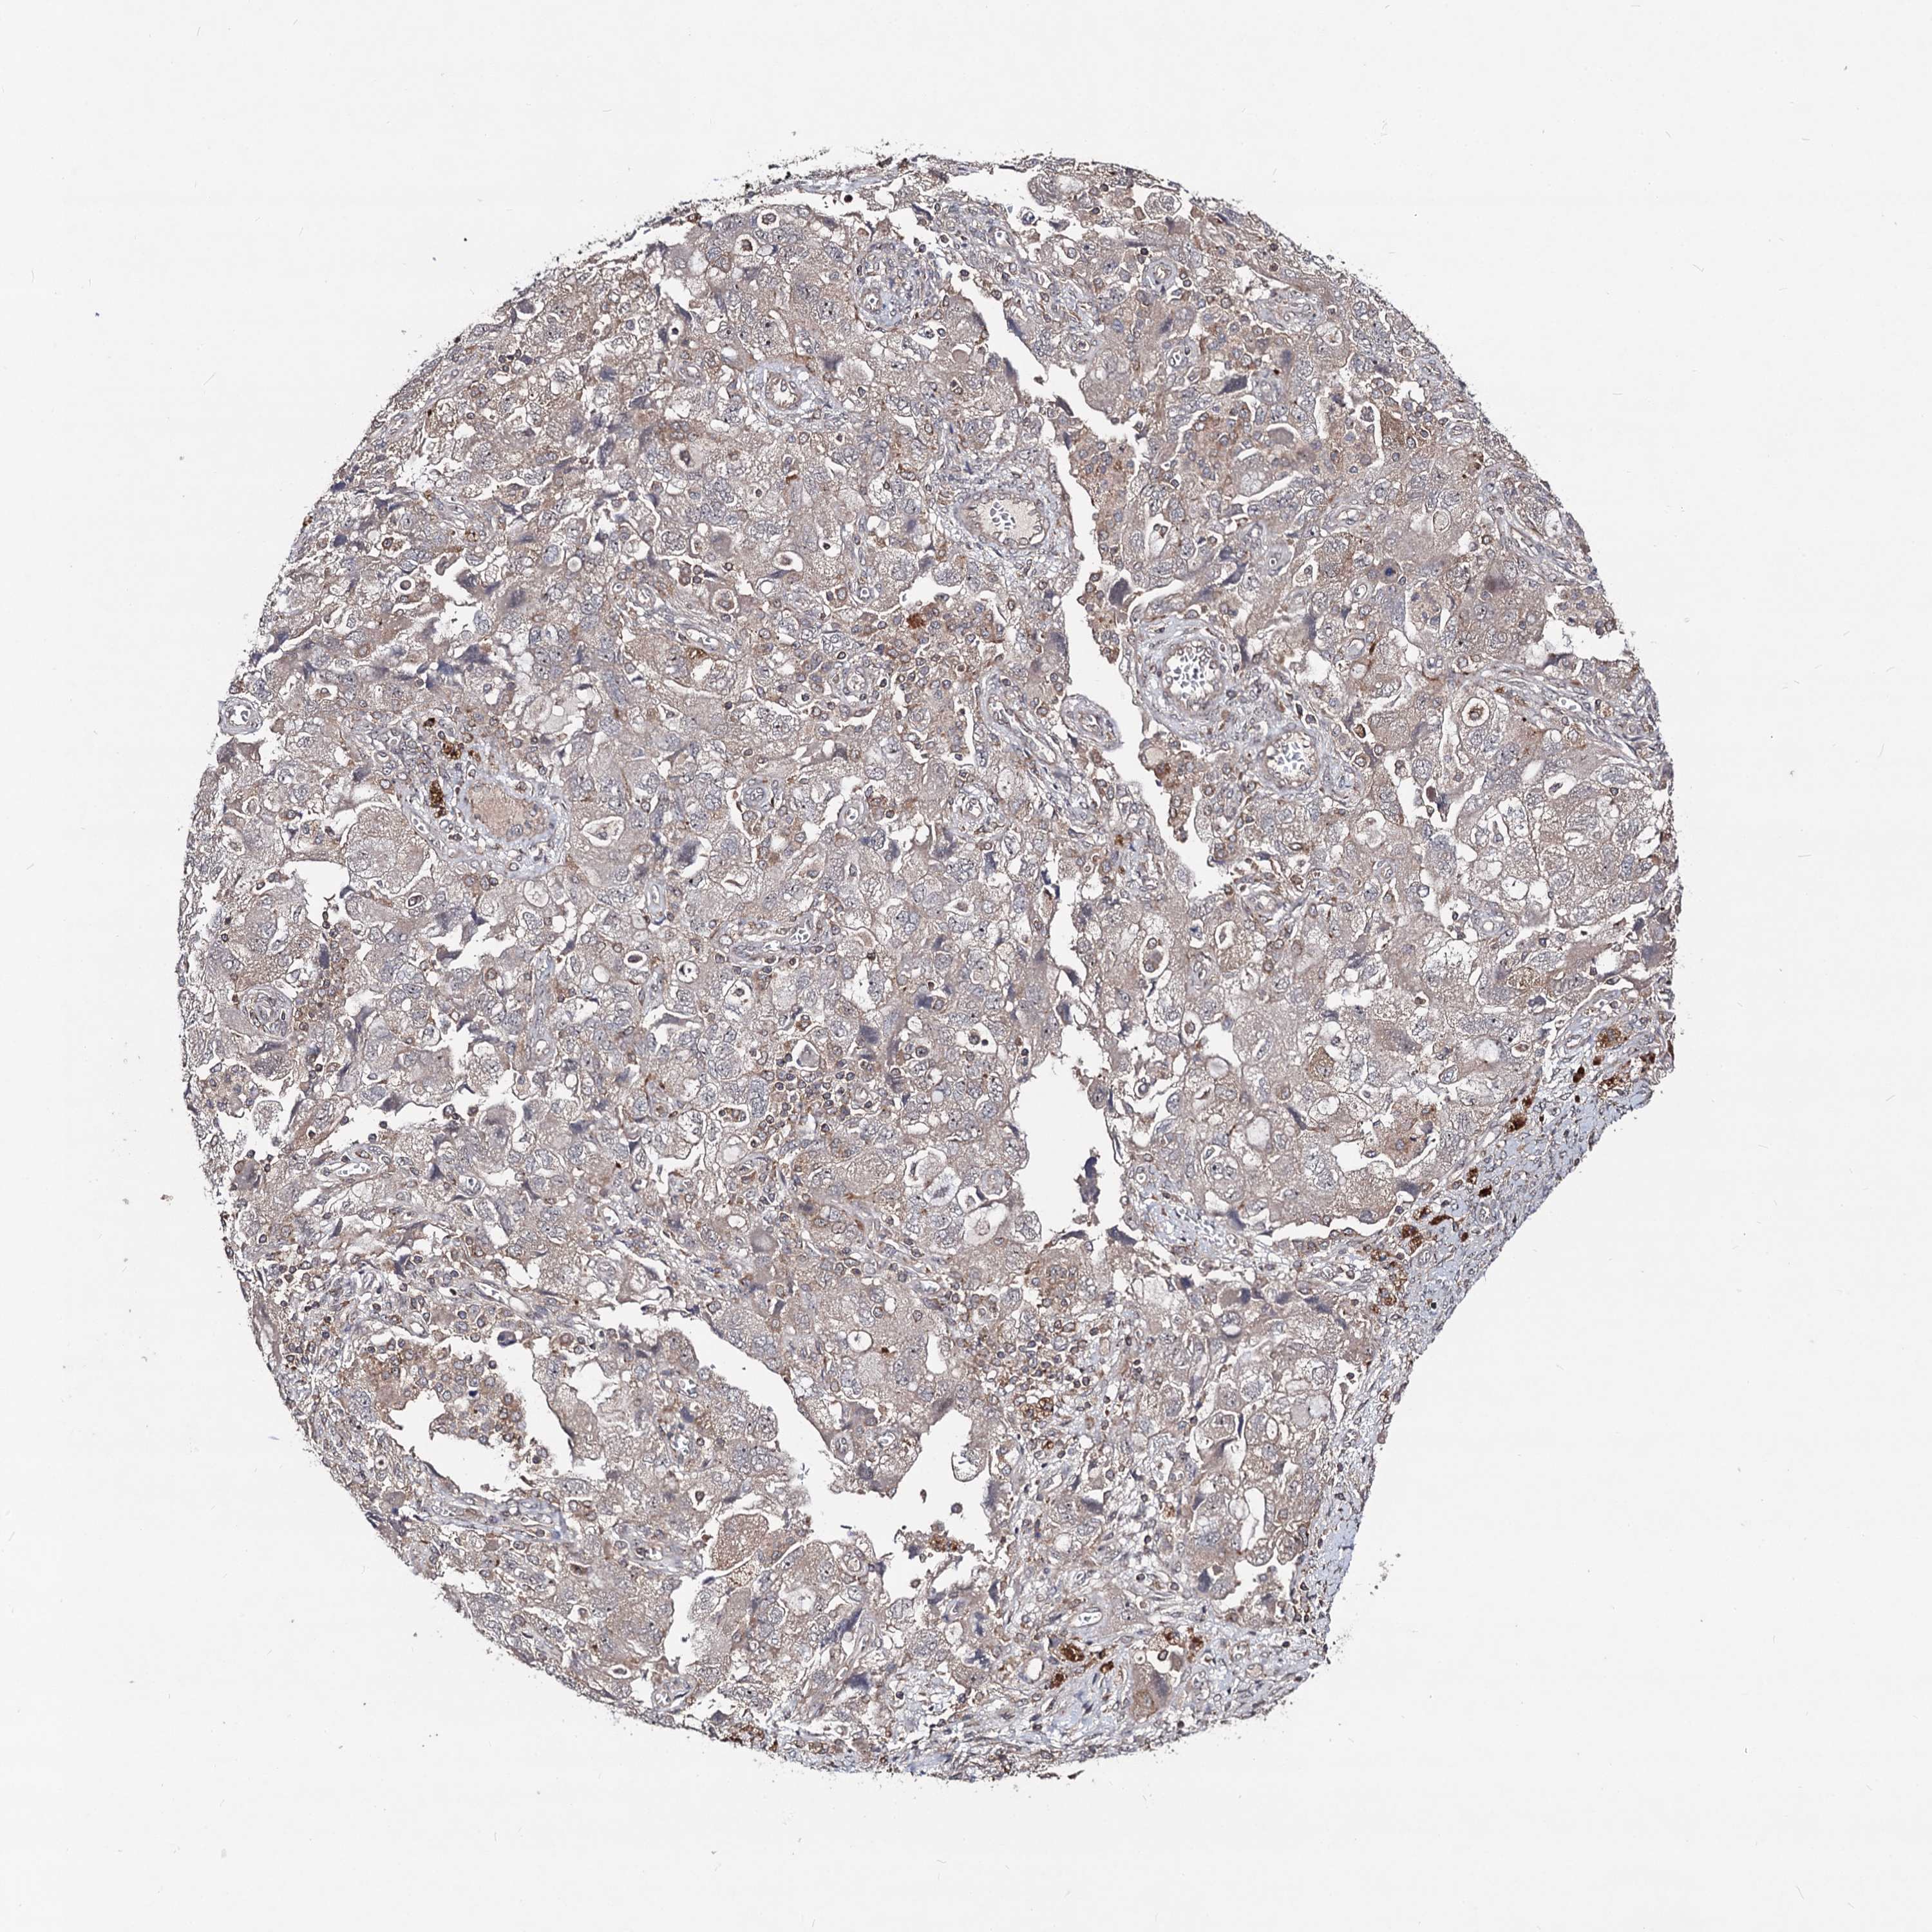

OVARIAN CANCER - Protein expressioni

A mouse-over function shows sample information and annotation data. Click on an image to view it in a full screen mode. Samples can be filtered based on level of antibody staining by selecting one or several of the following categories: high, medium, low and not detected. The assay and annotation is described here.

Note that samples used for immunohistochemistry by the Human Protein Atlas do not correspond to samples in the TCGA dataset.

Antibody stainingi

Antibody staining in the annotated cell types in the current human tissue is reported as not detected, low, medium, or high, based on conventional immunohistochemistry profiling in selected tissues. This score is based on the combination of the staining intensity and fraction of stained cells.

Each image is clickable and will lead to virtual microscopy that enables deeper exploration of all samples and also displays staining intensity scores, fraction scores and subcellular localization as well as patient and tissue information for each sample.

Antibody HPA041507

Antibody HPA041599

Cystadenocarcinoma, serous, NOS

Carcinoma, endometroid

Cystadenocarcinoma, mucinous, NOS

Carcinoma, NOS